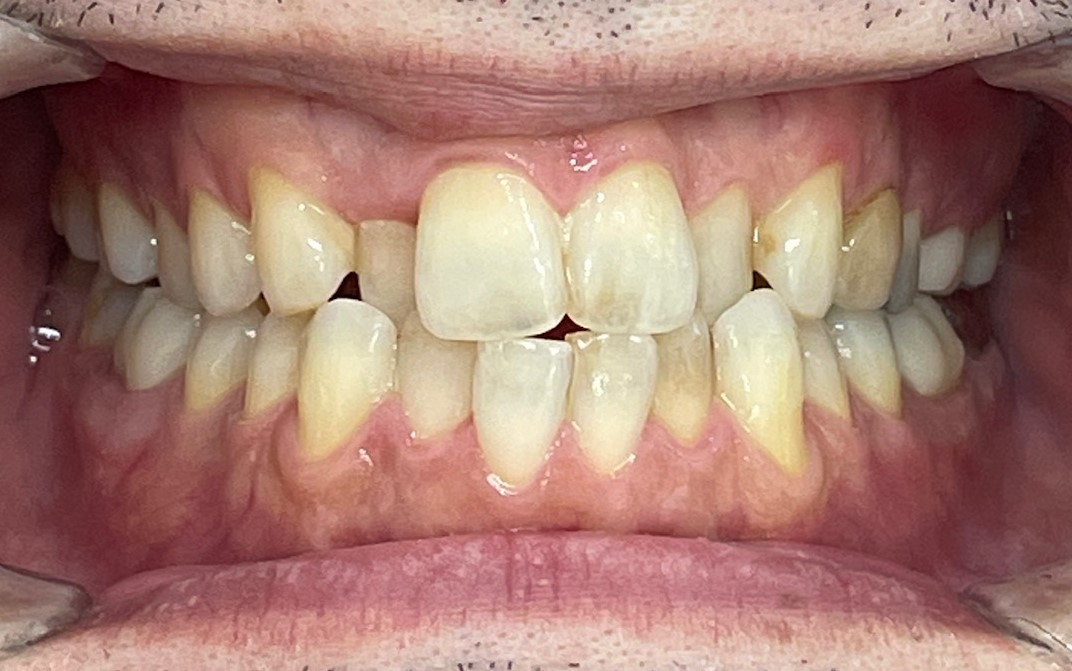

Before

After

矯正の種類 / invisalign GO

年齢・性別 / 30代女性

主訴  /  叢生、交叉咬合

治療期間 / 17ヶ月

費用 / 簡易検査 5,000円(税別) 精密検査 30,000円(税別)

両顎マウスピース 450,000円(税別) 両顎リテイナー料 60,000円(税別)

※マウスピース交換時別途調節料5,000円(税別)

副作用 / 口内炎・歯の移動に伴う痛み・知覚過敏 ※数日で収まる場合が多いです

リスク / 後戻り防止の為、夜のみマウスピースで保定を指示